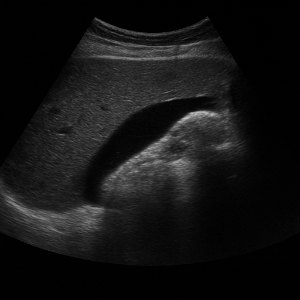

복부초음파에서 정상 소견은 “언리마커블(unremarkable)” 또는 “특이 소견 없음” 같은 표현으로 나타나요. 예를 들어 간, 췌장, 비장, 신장 등이 특별한 이상 없이 보이면 정상으로 간주되죠.

비정상 소견은 장기별 여러 모습으로 드러날 수 있어요. 대표적으로는 간에 종괴나 지방간, 담낭이나 담도에 돌이나 염증, 신장의 수신증(소변이 고이는 현상), 결석, 복수(복강 내 물) 등이 있고, 맹장염이나 충수염, 복강 내 농양, 동맥류도 발견될 수 있어요.